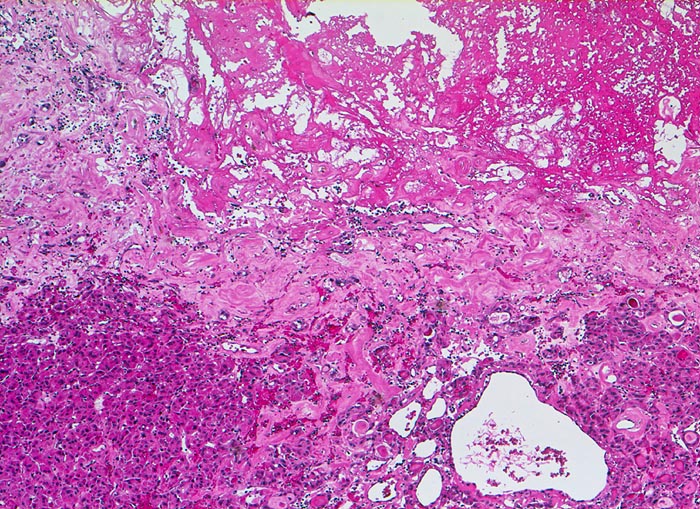

PathoPic – image database / PathoPic ID 5249 - follikuläres Schilddrüsenkarzinom

follikuläres Schilddrüsenkarzinom

Ausschnitt aus dem Tumor mit Fibrose und Einblutung (oben im Bild)

Histologie

50